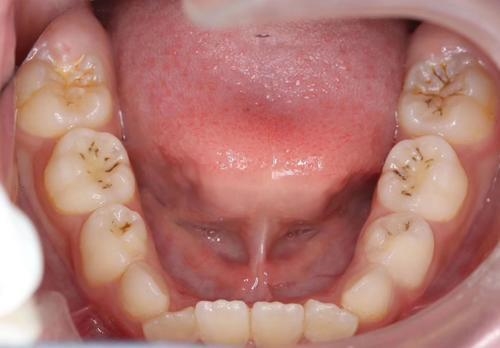

至于蛀牙嘛,早期的大牙有蛀牙是没有明显的龋洞,大多在咬合面有黑色的勾线,也就是窝沟龋,就是蛀牙的表现。所以一旦发生这样的情况都需要注意啦!别等到蛀牙很严重了,才去补牙。到时候已为时已晚了!

image003

窝沟龋的发展主要有三个阶段

1.牙齿表面形成黑线,初步形成蛀牙,这个阶段是蛀牙早期。

2.牙本质腐蚀,龋坏进一步加深,形成龋洞,牙齿冷热酸疼,此为蛀牙中期。

3.龋坏影响牙髓,出现明显的疼痛,龋洞更大,此时可采用根管治疗,去除龋坏部分,充填材料,尽可能保真牙。